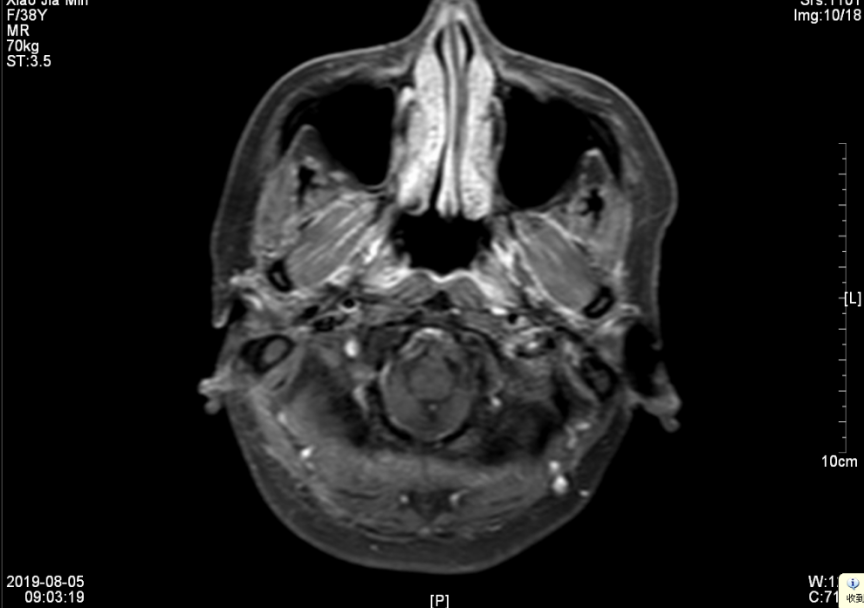

第4程化疗结束后前往外院就诊,行TP化疗2程,后联合尼妥珠单抗同步放化疗(局部放疗共34次,各靶区计划照射:PGTVnx:70.4Gy/2.2 Gy/32f,PCTV1:64.0Gy/2.2 Gy/32f,PCTV2:57.6Gy/1.8Gy/32f,PGTVnd:68.8Gy/2.15 Gy/32f,最后一次放疗于2019年6月28日结束。2019年7月复查颈部+鼻咽增强MRI:1、鼻咽癌综合治疗后复查,与前片(2019年03月11日)比较,鼻咽病灶及转移淋巴结较前明显缩小、减少(大小约11mm×16mm×18mm);颅底及颈部软组织水肿考虑放疗后改变。2、副鼻窦炎,右侧中耳乳突炎。(见图五、图六)

▲图五 2019年8月5日 放化疗后淋巴结MRI(18mm×16mm)

▲图六 2019年8月5日 放化疗结束1月鼻咽部MRI(病灶消失)